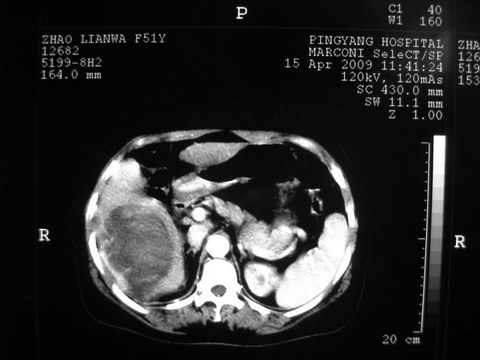

患者 女 51岁 两天前感觉上腹疼,无明显诱因,b超示肝右叶囊实性占位,边缘清楚,其内回声不均匀,ct增强如图,大家看看是什么 ,病人一年前及两月前b超检查只是提示胆囊炎

外院术后,证实肝癌合并出血

特点:1,病灶发展迅速,(2月前正常)[br] 2,囊实性,且并边界清晰光滑,呈右后叶赘生性。囊性区无强化,实性部分较多轻度强化,边界欠清。考虑囊腺癌或囊腺瘤。

出病理 中分化肝细胞癌合并出血